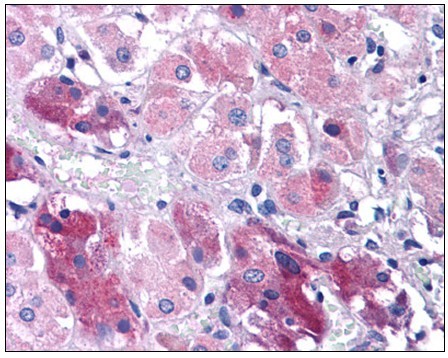

Supportive validation

- Submitted by

- Acris Antibodies GmbH (provider)

- Main image

- Experimental details

- Human Adrenal: Formalin-Fixed, Paraffin-Embedded (FFPE)